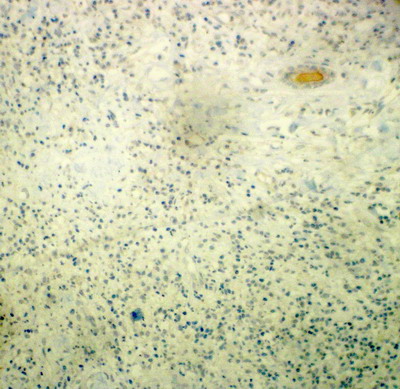

Immunohistochemical studies showed tumor cells were strongly positive for CD68 (Fig.4), Focal positivity for CD20 (Fig.5) and CD15 (Fig.6) and negative for CD30 (Fig.7) and ALK (Fig.8).

Fig 4: CD68 immunohistochemical stain showed strong diffuse cytoplasmic staining for histiocytes cells [X 160]